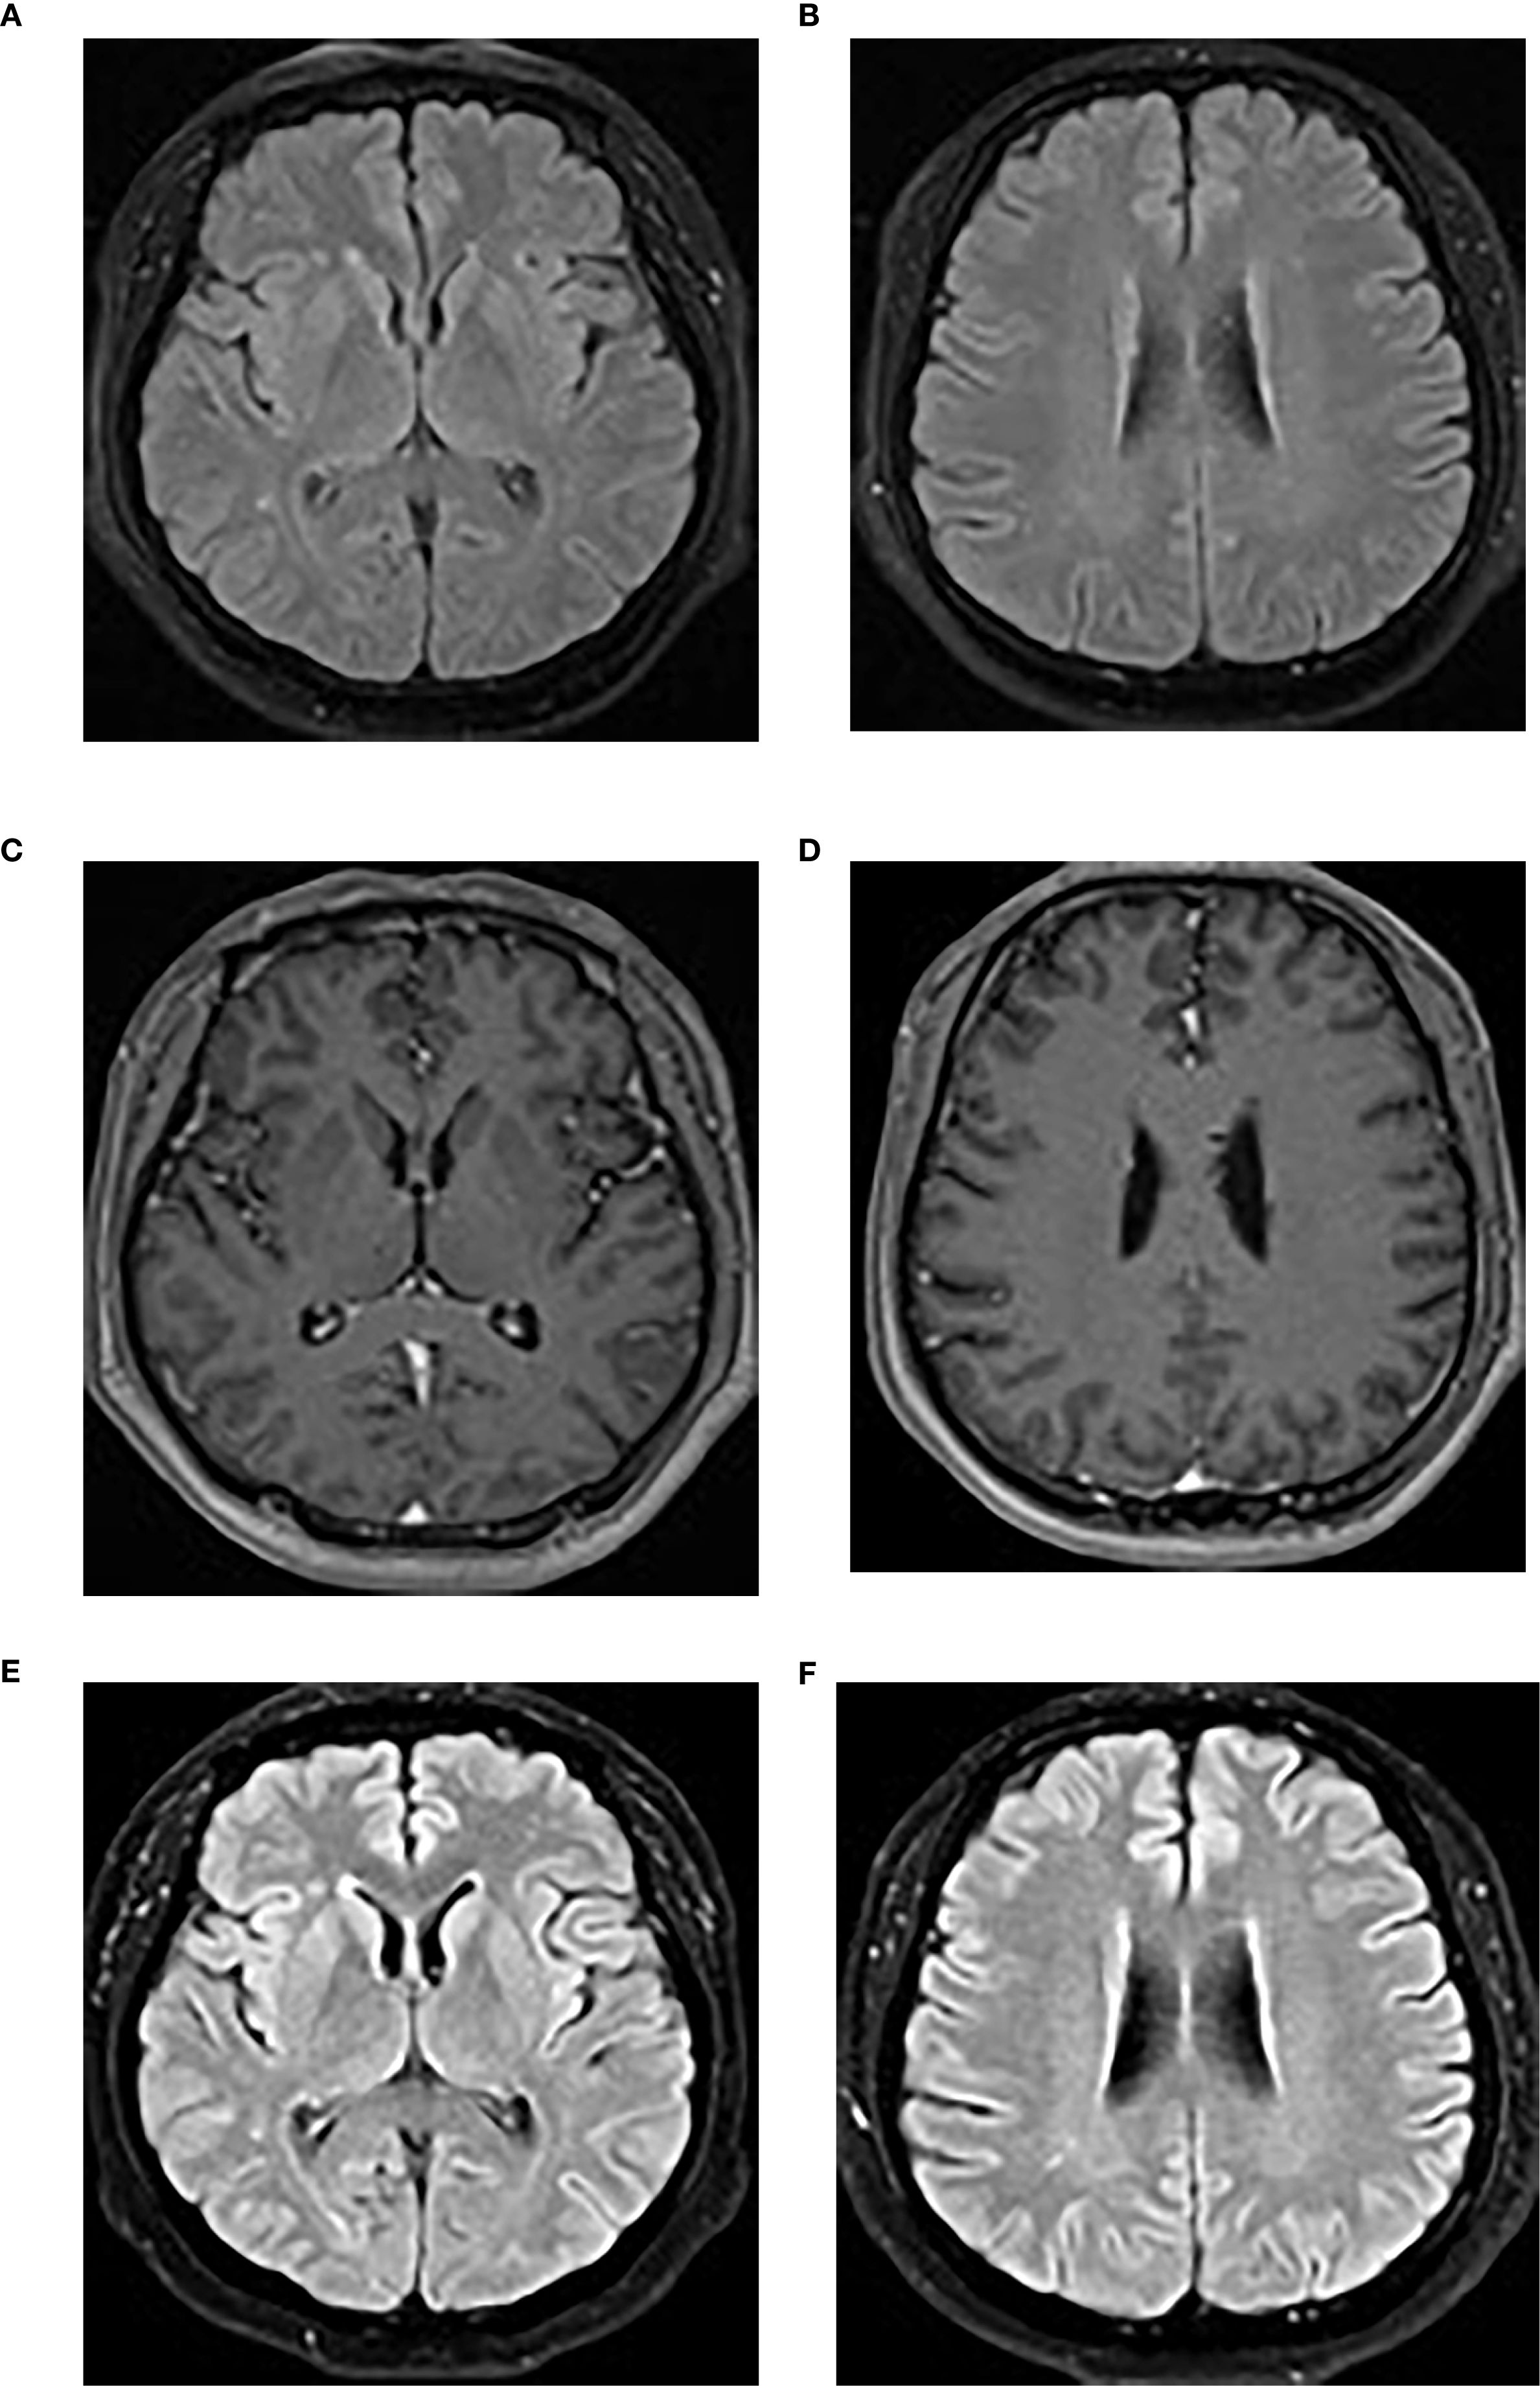

A brain MRI revealed bilateral frontal and parietal subcortical and periventricular scattered punctate lesions with T1 hypointensity, T2 hyperintensity, and T2-weighted fluid-attenuated inversion recovery (FLAIR) hyperintensity without abnormal enhancement or diffusion restriction, suggesting white matter demyelination changes (Figure 3).

Figure 3. (A, B) The initial brain MRI image demonstrated scattered punctate T2-FLAIR hyperintensities in the bilateral frontal and parietal subcortical and periventricular regions. (C, D) Post-contrast T1-weighted imaging showed no abnormal enhancement. (E, F) A repeat brain MRI performed at the 4-month follow-up showed no significant changes on the T2-FLAIR sequence. T2-FLAIR, T2-weighted fluid-attenuated inversion recovery.

Over 1 year of intermittent follow-up during immunosuppression, no relapse occurred, cognitive impairment improved significantly (MoCA score 29/30), serum inflammatory markers normalized, and CSF parameters trended toward normal, with the exception of mild CSF leukocytosis (Table 1). A 4-month follow-up brain MRI showed no significant changes (Figures 3E, F). Anti-GABABR IgG titers were not reassessed due to patient refusal.